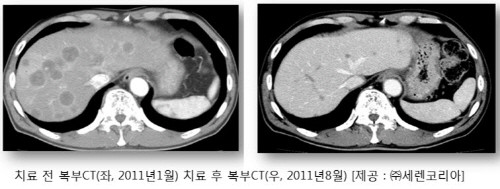

강연회에 앞서 한 췌장암 환자의 임상사례를 짧게 소개한다. 68세인 남성으로 지난 2011년 1월에 수술불능의 췌장암 말기로 진단돼 수지상세포 백신요법을 4월부터 받기 시작했으며, 세렌클리닉 그룹 의료진의 철저한 분석과 치료 경험에 근거한 개인 맞춤별 치료도 병행을 했다.

종양표지자(CA-19-9) 수치가 9개월 만에 18만에서 0에 가깝게 개선이 됐고 간에 다발성으로 전이된 종양도 거의 사라져 버렸다. 지난 2011년 6월에 종양이 남아 있는 췌장 말단을 제거하는 수술을 받게 됐고 현재까지 건강하게 일상생활을 하고 있다.